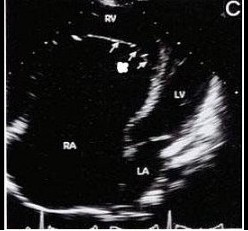

如图三尖瓣病例最可能的诊断

A、右室双腔

B、三尖瓣缺如

C、异位腱索

D、三尖瓣下移

E、室间隔缺损

D